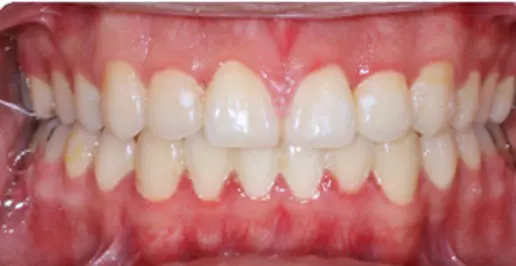

Before

After